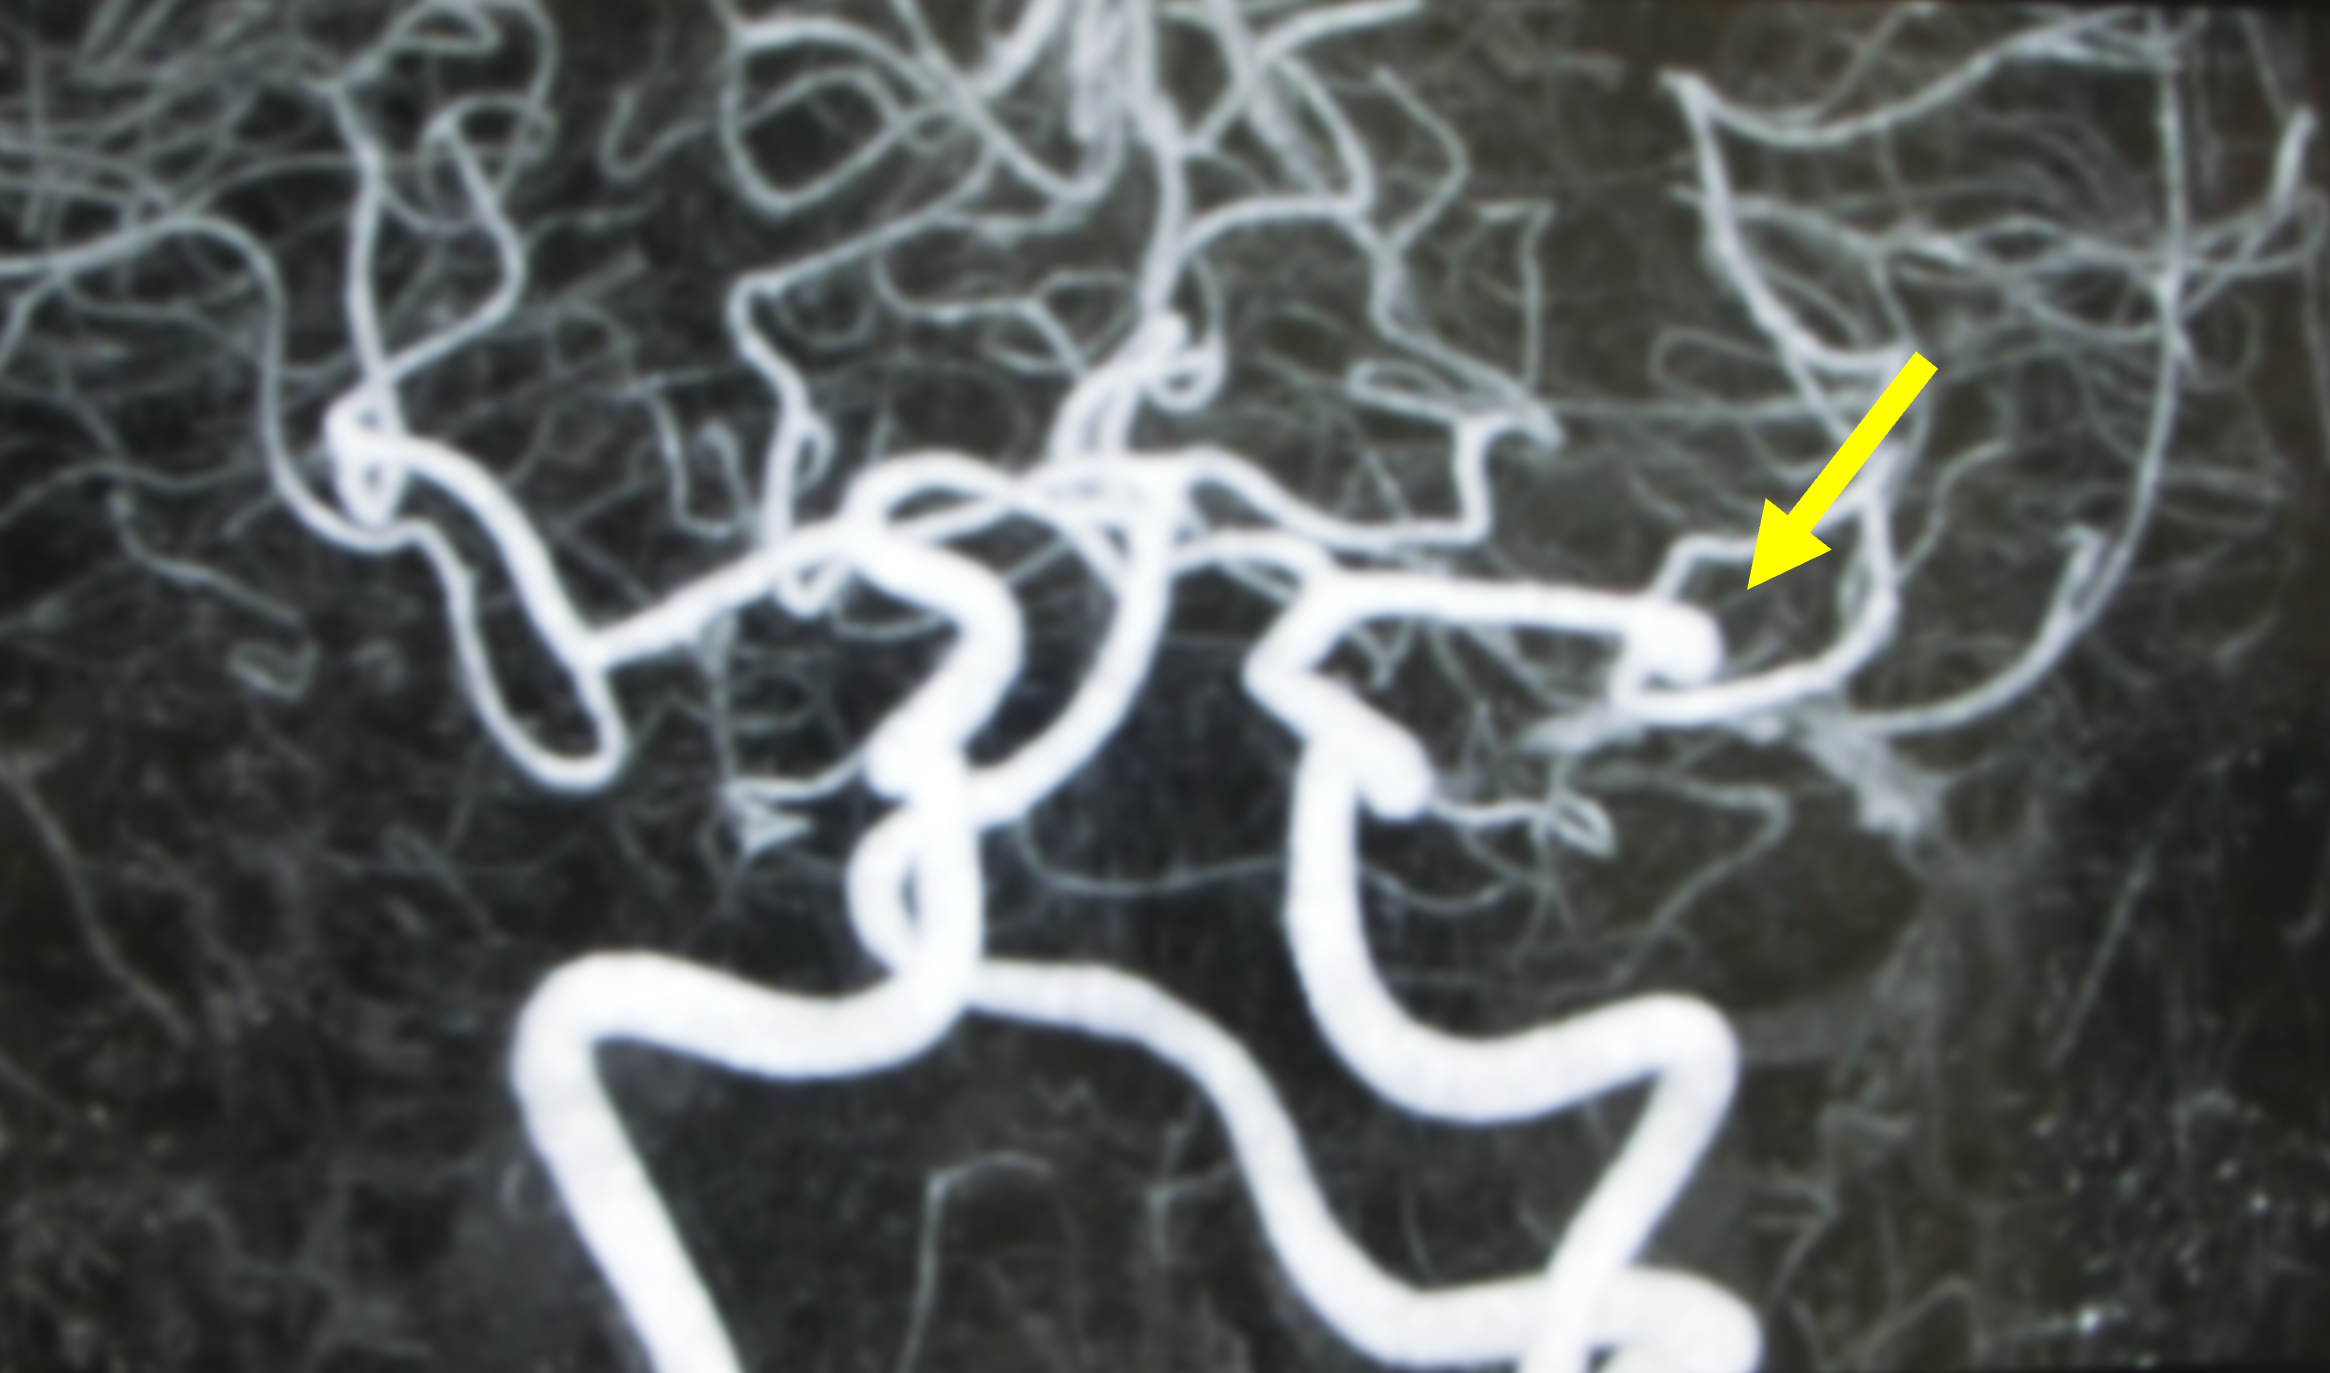

MRA検査画像

脳の血管を見ることができます。動脈瘤や動脈硬化による狭窄や閉塞の診断に役立ちます。

脳動脈瘤(矢印):脳の血管の壁が膨らんでこぶ状に見えます。膨らんでいる部分が破れるとくも膜下出血になります。

脳MRI・MRA検査による脳ドックでは、脳卒中の原因となる脳動脈瘤や脳動脈の狭窄を見つけることができます。